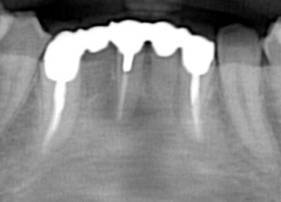

過重負担のブリッジ

右下 7 番(第二大臼歯)から左下 3 番(犬歯)までの 10 本の歯を 4 本の根でささえています。このような場合、完全に支える根の強度不足により、歯根破折あるいは根周囲の骨吸収が急激に生じる(咬合性外傷)可能性があります。